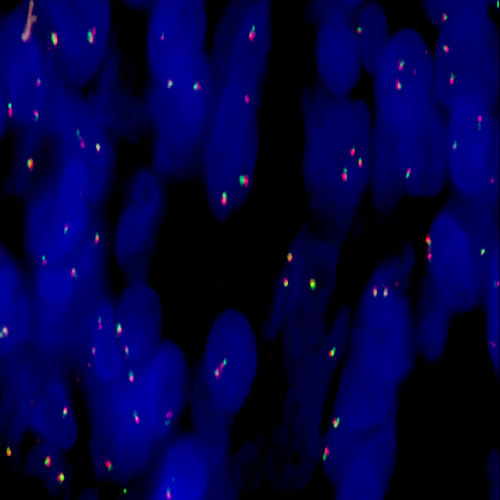

Diffuse Large B-Cell Lymphoma stained using Kreatech MYC (8q24) Break

XL probe for BOND (KBI-XL006).

MYC (8q24) Break - XL for BOND FISH probe detects genomic translocations involving the MYC gene. MYC (8q24) Proximal - XL and MYC (8q24) Distal - XL are optimized to detect the genomic regions proximal and distal to break points in the MYC gene region. When combined, both probes are used to detect translocations involving the MYC gene at 8q24.